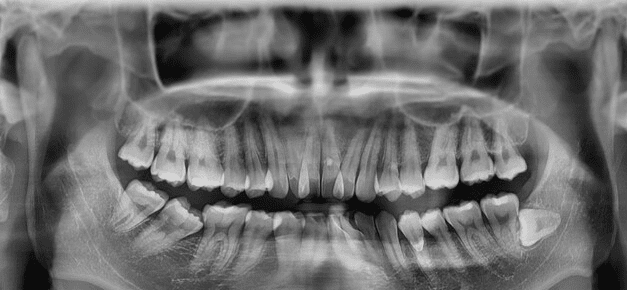

- X光檢查:X光片是診斷阻生智齒的重要手段。常用的X光片包括全景片、根尖片等。全景片可以清晰地顯示智齒的位置、方向、阻生類型以及與鄰牙的關係;根尖片則可以更詳細地觀察智齒的牙根形態和周圍骨組織的情況。